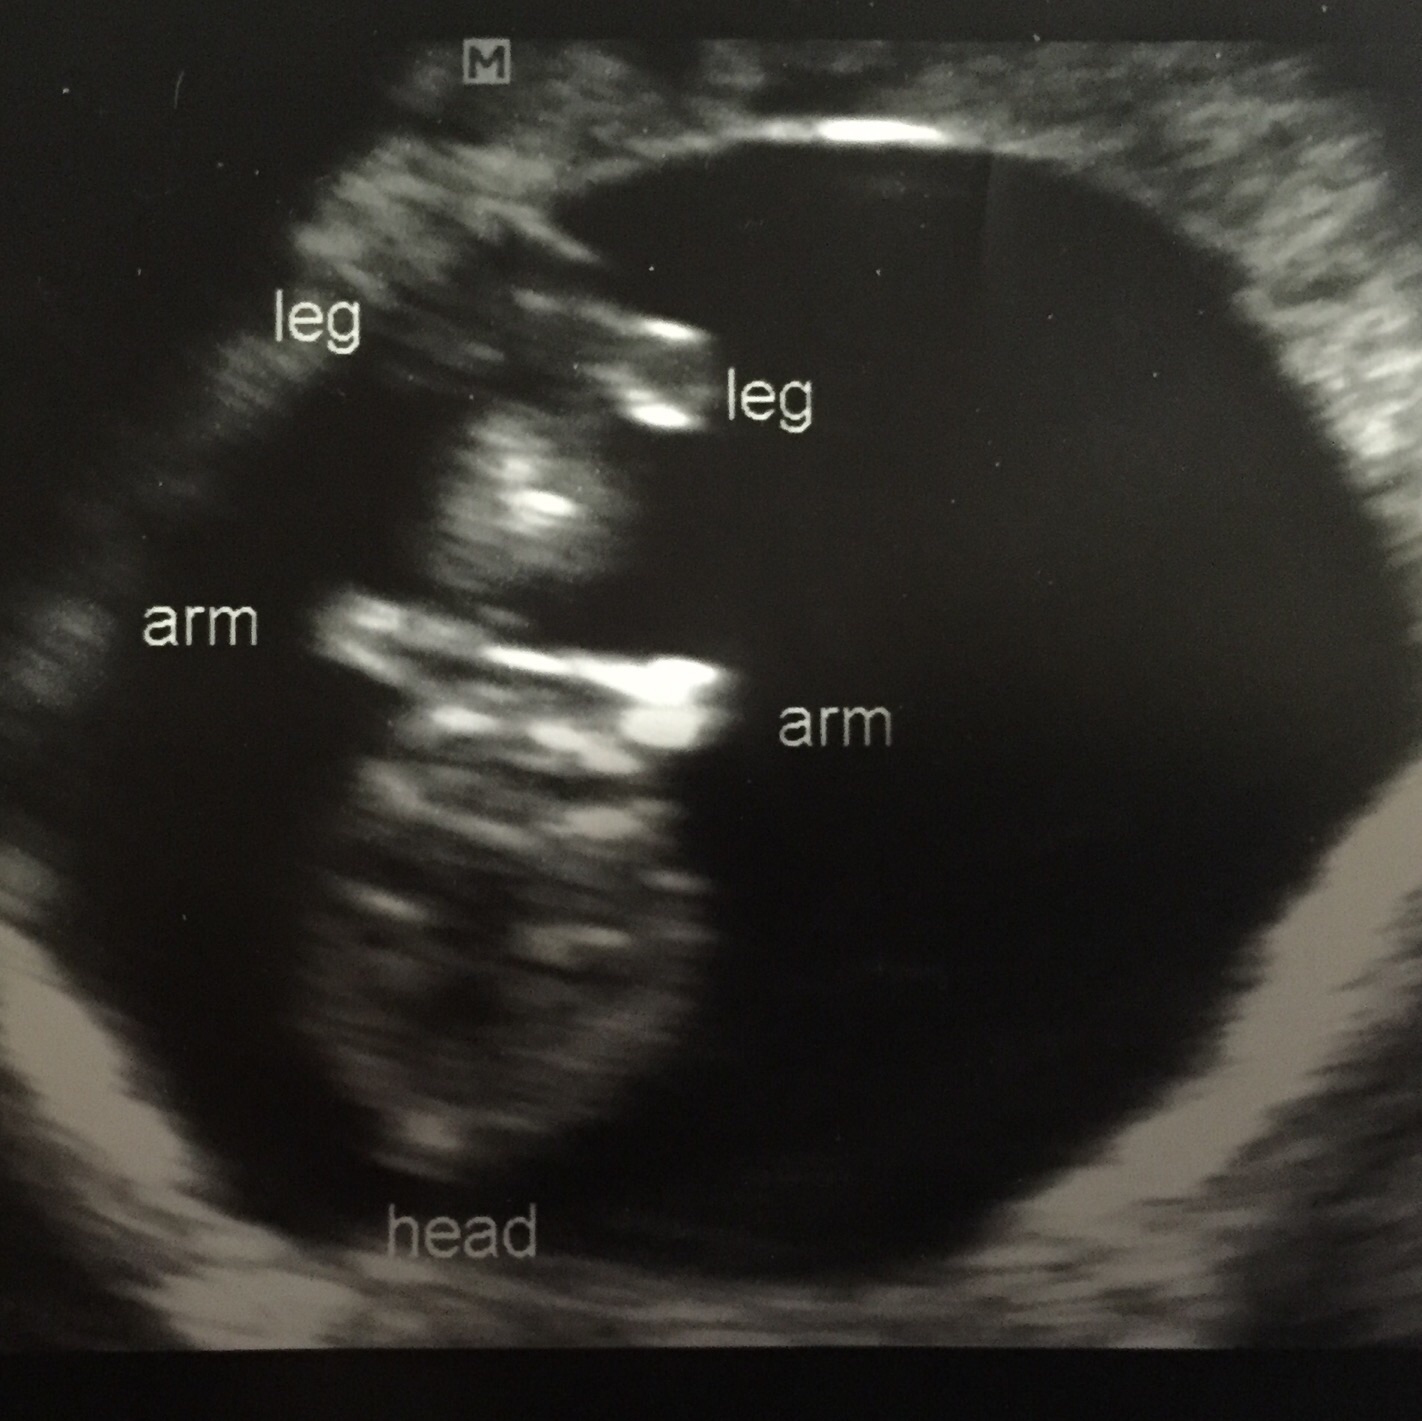

Had my second ultrasound today. Measuring 9w+2d. Baby was moving around so much! Looked like it was doing the robot It was my husband's first time seeing and hearing the heartbeat (167). Feeling so relieved since my morning sickness had really gotten better and I was getting worried..